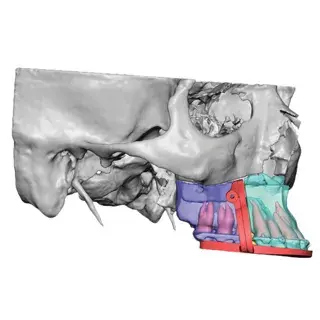

3D Systems' VSP® surgical planning solutions for craniomaxillofacial (CMF) applications received FDA clearance as a service-based approach to personalized surgery over 10 years ago.

3D Systems and Stryker Corporation have partnered to provide surgeons with best-in-class products and services for craniomaxillofacial surgeries. As a leader in personalized healthcare solutions, 3D Systems has planned and delivered devices for more than 140,000 patient-specific cases. The Stryker Craniomaxillofacial business specializes in providing patient-specific options and innovative solutions that help drive efficiencies in surgical suites. The combination of Stryker’s specialized team and advanced implants with 3D Systems' cutting-edge 3D printing technologies and expert consulting services positions both companies to provide a superior level of service to healthcare professionals who use these revolutionary solutions.